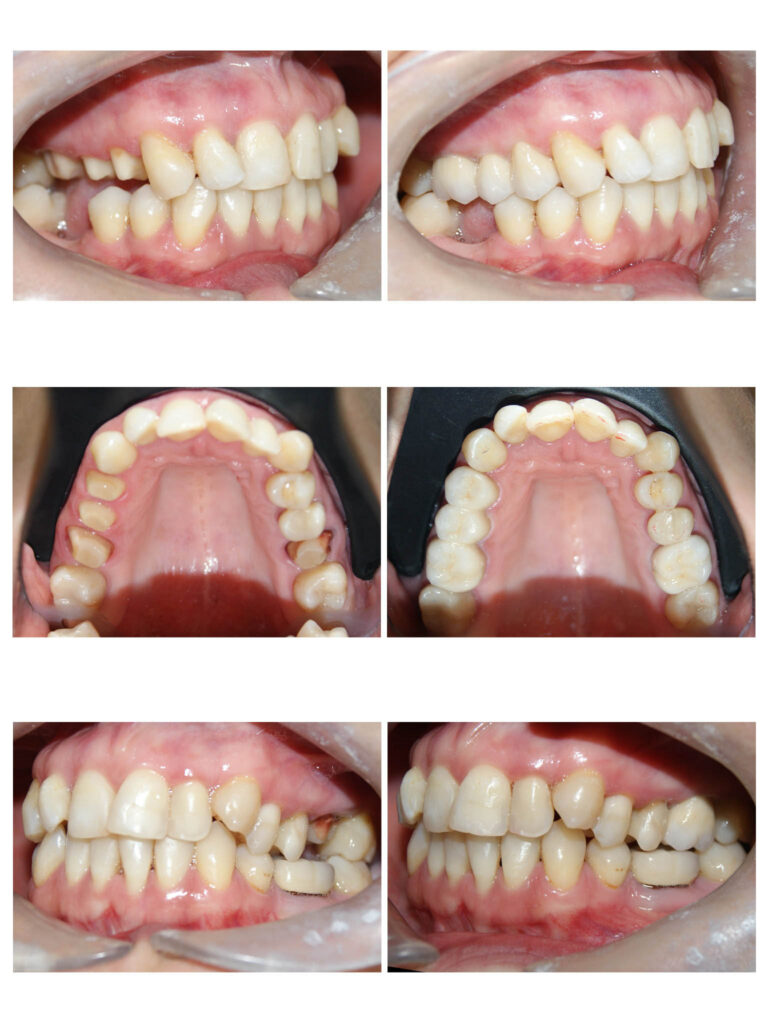

Crearea spațiului pentru alinierea dinților și pentru corectarea mușcăturii încrucișate.